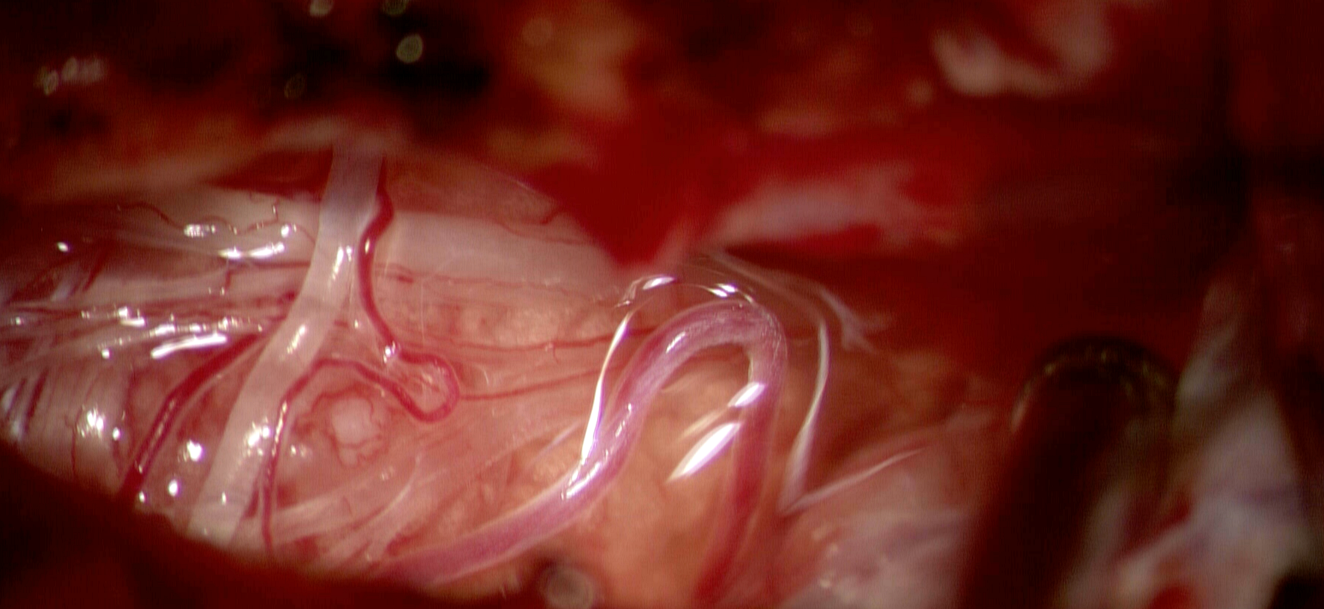

Intervenția chirurgicală s-a desfășurat sub anestezie generală, folosind tot arsenalul de aparatură medicală neurochirurgicală: neuronavigație, microscop operator, disector ultrasonic, instrumentar microchirurgical, etc. Abordul a fost printr-un volet pterional minim-invaziv drept (de partea emisferului nedominant), fără a rade părul (doar o cărare îngustă de-a lungul inciziei) și fără a utiliza retractoare cerebrale fixe, care pot produce leziuni ale creierului. Pentru că accesul latumoră se face pe sub lobul frontal, de maximă importanță în aceste operații este o bună anestezie care să asigure relaxare creierului și scăderea presiunii intracraniene.

Operația a durat aproximativ 3 h și si-a atins scopurile în totalitate – rezecția completă a tumorii cu coagularea zonei de inserție meningeală și păstrarea integrității structurilor cerebrale normale, inclusiv a celor doi nervi olfactivi, care erau doar deplasați de tumoră, nu invadați.